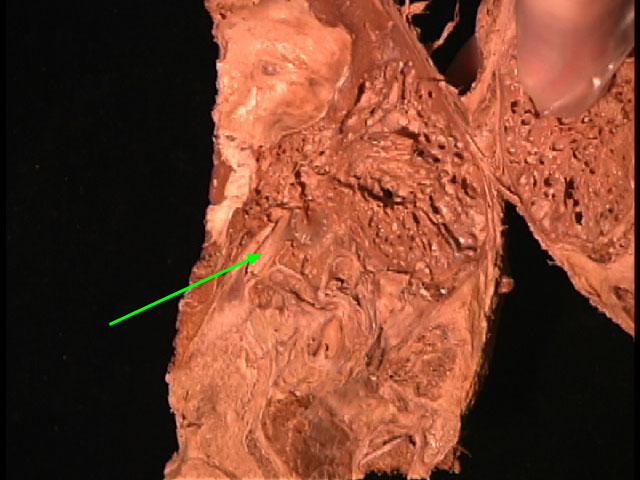

Identify the structure marked by the arrow

Facial canal

Stapes

Internal Acoustic Meatus

Vestibular (Oval) Window

Geniculate Ganglion

Inferior Tympanic Canaliculus

Cochlea

Incus

Epitympanic Recess

Mastoid Antrum

Malleus

Tympanic Membrane

Tegmen Tympani

Stapedius m.

External Acoustic Meatus

Auditory Tube

Tensor Tympani m.

Promontory

Vestibulocholear n.

Semicirular Canals

Facial n.

Petrotympanic Fissure

Cochlear (Round) Window

Chorda Tympani

Greater Petrosal n.

Lesser Petrosal n.